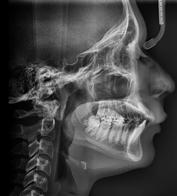

Estudios iniciales radiográficos de inicio

En la radiografía lateral de cráneo ( Figura 6 ) se ve la línea estética de Rickets, que el labio superior se encuentra a +0.5 mm y el inferior a -2 mm. En las mediciones cefalométricas más importantes en la figura 11 un ANB de 5º, GoGn-SN de 33º y FMA de 21º crecimiento normodivergente y Witts de -1 mm. A los criterios dentales encontramos

1-PLT de 129º e IMPA 99º proinclinación de incisivos tanto superiores como inferiores. En la radiografía panorámica (Figura 7), la presencia de 32 órganos dentarios, con terceros molares inferiores aún sin erupcionar y terceros molares superiores

Figura 6. Rx. cráneo lateral inicio progreso con trazos.

7. Radiografía panorámica.

Secuencia de radiografías laterales de cráneo (Figura 15) vemos que el ANB disminuyo 1º de inicio a fin clase I con tendencia a clase II esquelética a final. Reducción de Witts 0.5 mm final, crecimiento normodivergente. Mandíbula más pequeña que el maxilar, cambio por el avance mandibular.

Figura 15. a) Rx lateral de cráneo de inicio. b) De progreso. c) Lateral de cráneo final.